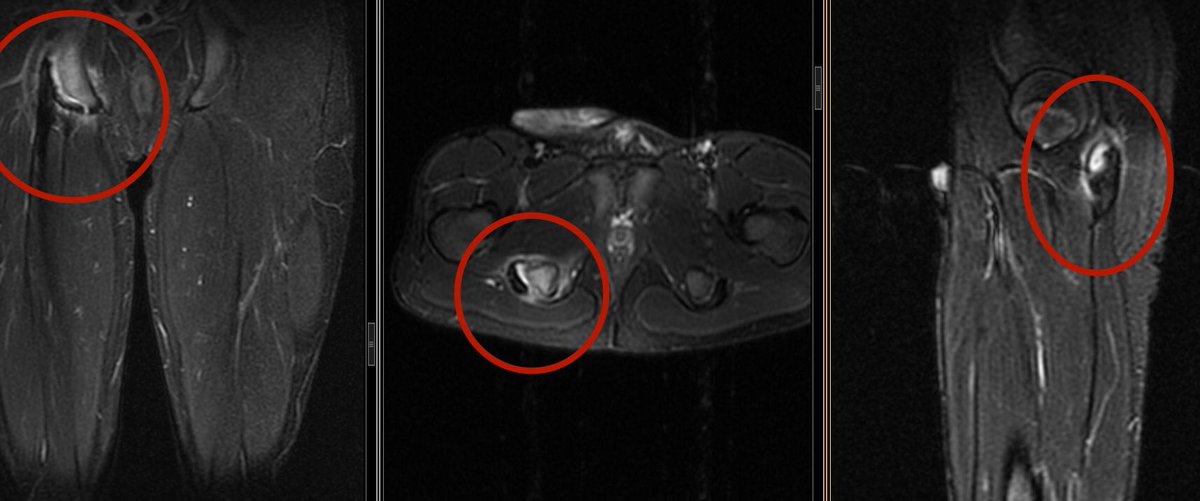

12 yo boy with buttock pain after soccer game

* Ischial tuberosity avulsion fracture

Easily missed on X-ray

Usually conservative when displaced <2 cm

#mskrad#sportsmedicine#Orthopedics#radiology#radiologiapic.twitter.com/inQAM3aOqg